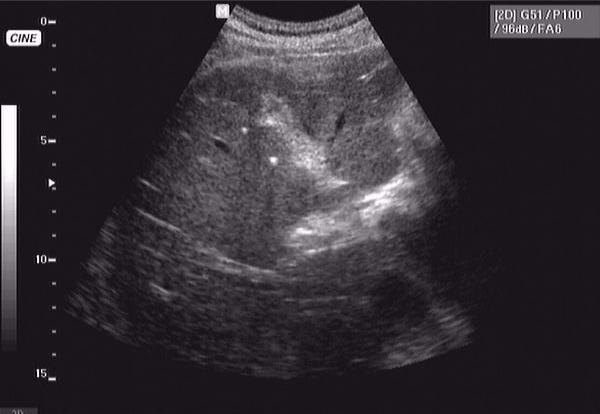

76 летний пациент - конкремент желчного протока, печень правая - 178 мм, левая - 62 мм

сахарного диабета нет, зато есть уртикарная сыпь... шистосомоз?

Онищук76 33.JPG

Онищук76 44.JPG

Онищук76 11.JPG